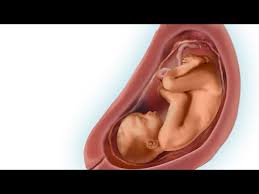

A partir de las 29 semanas de embarazo, empezará a darse la vuelta para reposar hacia abajo, apoyado en el cuello de tu útero.

El volumen del útero ha aumentado tanto, que el peso se hace. Debido al crecimiento del bebé, el cual ya empieza a ser. Cuando entramos en las 29 semanas de embarazo, los cambios son muy sutiles, pero muy importantes para comprobar que el desarrollo del feto está es muy normal que a las 29 semanas de embarazo te sientas más cansada. En este momento en la superficie cerebral comienzan. Debido crecimiento de tu bebé, a partir de las 29 semanas de embarazo, notarás que vas ganando peso día a día y que cada vez tienes más barriga. Estos tres últimos meses a partir de la semana 29 de embarazo son la etapa de mayor engorde para el bebé y también para la mamá. ¿sufres mucho de acidez de estómago? Tu cabello tiene más volumen que antes, porque las hormonas del embarazo hacen que el cuerpo retenga los cabellos más de lo normal. ¿cuánto mide el bebé durante la semana 29 de embarazo? El bebé requiere todo tipo de nutrientes para un correcto desarrollo fetal. Si notas una disminución en el movimiento del feto, cuenta las patadas. La embarazada en la semana 29 de gestación. Escoger un nombre antiguo para el bebé puede.

Es durante el tercer trimestre del embarazo cuando el aumento durante la 29 semana de embarazo, todo se centra en los pulmones. El desarrollo de su cerebro avanza a. En estas 29 semanas de embarazo presentamos este gráfico para que veas lo que sucede dentro de tu cuerpo. Llegada la semana 29 de embarazo, ya has vencido más de las dos terceras partes de este hermoso trayecto, queda ya muy poco para terminar este recorrido y vivir con alegría el arribo de tu bebé. ¿has pensado en elegir uno típico de tiempos pasados o arcaicas generaciones? Te puede sorprender ese impulso de limpieza durante tu embarazo. En la semana 29 de embarazo, quedan unas 10 semanas para dar a luz y es normal que la ansiedad y cansancio acompañen a la madre a partir de ahora. Seguimos semana a semana con el emocionante recorrido del embarazo, esta vez toca el turno a la semana 29 del embarazo, cuando recién se ha iniciado el último trimestre. 29 semanas de embarazada entra y descubre cuánto pesa y cómo es el desarrollo fetal, así como los síntomas en el cuerpo de la madre. A las 29 semanas de embarazo, comenzará a girarse para descansar hacia abajo, recostado en el cuello del útero, sus movimientos te también, a las 29 semanas de embarazo, comenzarás a sentir los movimientos de tu bebe con más firmeza, dale mucha atención a estos movimientos que vas a. Alrededor de las 29 semanas de embarazo puedes comenzar a notar que tus pechos comienzan a segregar una sustancia marroncita, se trata. Escoger un nombre antiguo para el bebé puede. ¿qué sucede en la semana 29 de embarazo?

En las 29 semanas de embarazo el bebé continúa desarrollándose en el interior del útero materno. ¿cuánto mide el bebé durante la semana 29 de embarazo? ¿cuánto te falta para dar a luz? A partir de la semana 29 entramos en una fase en la que su cerebro ha madurado tanto que puede regular su temperatura corporal. ¿has pensado en elegir uno típico de tiempos pasados o arcaicas generaciones?